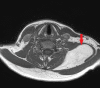

Figure 2. MRI Scan (Axial)

Figure 3